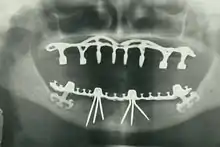

- Oral and maxillofacial radiology – The study and radiologic interpretation of oral and maxillofacial diseases.

By nature of their general training, dentists, without specialization can carry out the majority of dental treatments such as restorative (fillings, crowns, bridges), prosthetic (dentures), endodontic (root canal) therapy, periodontal (gum) therapy, and extraction of teeth, as well as performing examinations, radiographs (x-rays), and diagnosis. Dentists can also prescribe medications such as antibiotics, sedatives, and any other drugs used in patient management. Depending on their licensing boards, general dentists may be required to complete additional training to perform sedation, dental implants, etc.